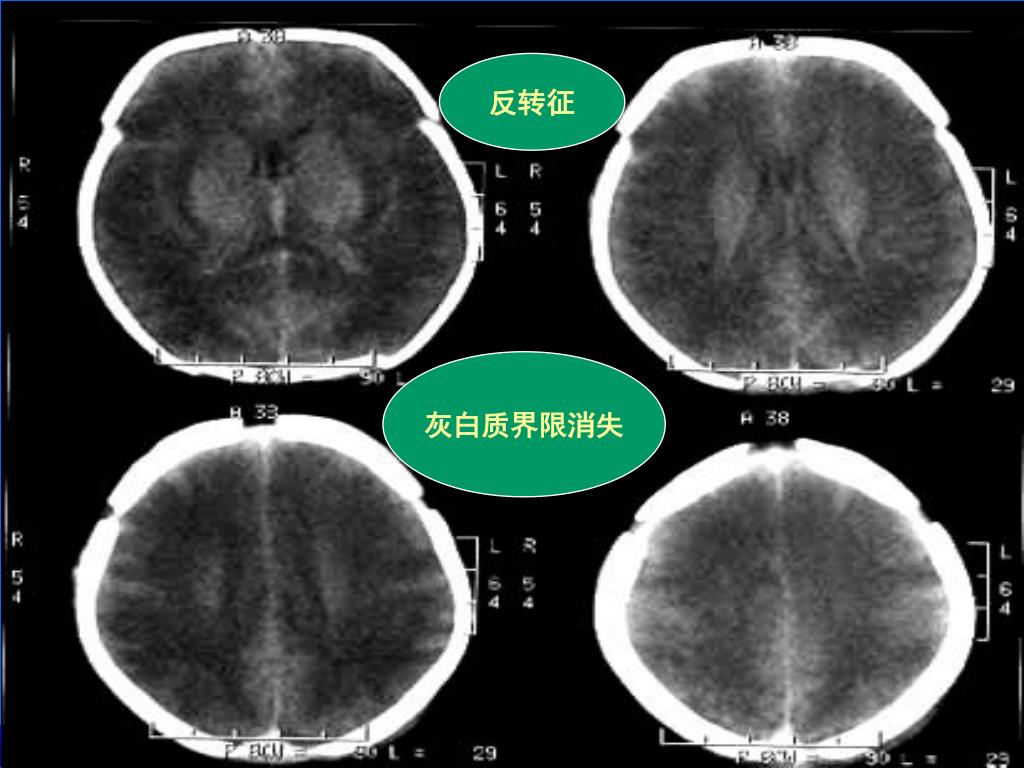

36. 反转征 灰白质界限消失

44. 反转征 灰白质分界模糊 中度HIE并少量蛛血

10. 附1:对低密度区的认识   (3)由于脑水肿以脑室旁周围白质为主;脑干、丘脑、基底节区和小脑不易受累。故小脑、脑干、基底节和丘脑的密度相对增高,形成所谓的“反转征”及“白色小脑征”。